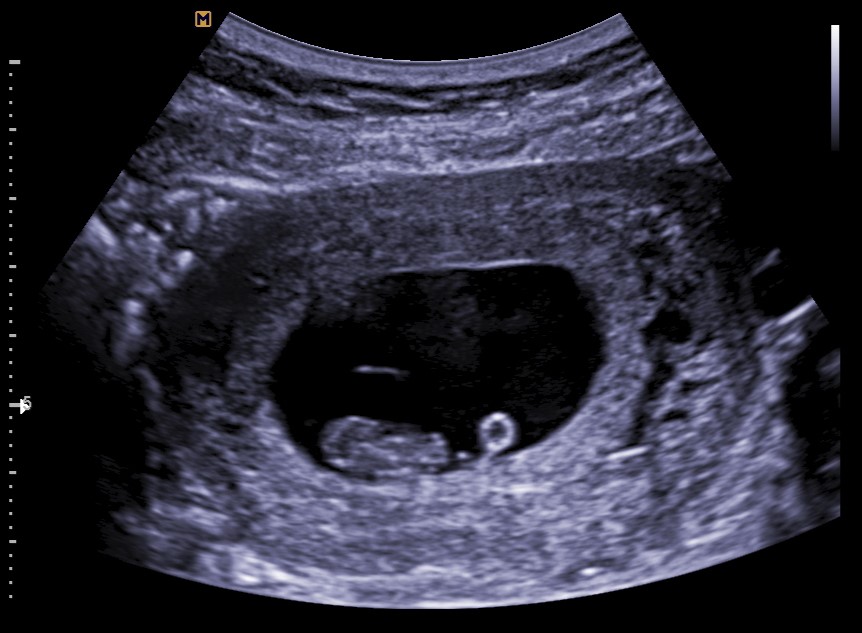

Vitaliteitsecho

Deze echo is bedoeld om te kijken of er hartactie te zien is, de zwangerschap zich in de baarmoeder bevindt en of er sprake is van een één- of meerlingzwangerschap. In dit stadium kunnen we nog niets zeggen over de gezondheid van de baby. De echo wordt rond de 8 weken zwangerschap gemaakt. Doorgaans zal deze echo inwendig gedaan worden omdat het kindje nog te klein is om via de buikwand te zien.